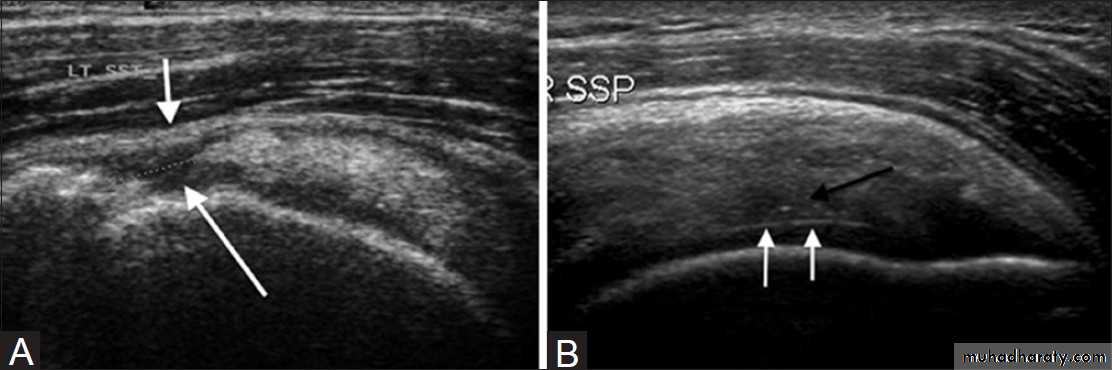

Best method of diagnosis. It shows the cuff tearUltrasound

May show cuff tearTreatment